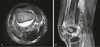

Brodie abscess

subacute osteomyelitis characterized by central lucency and peripheral sclerosis.